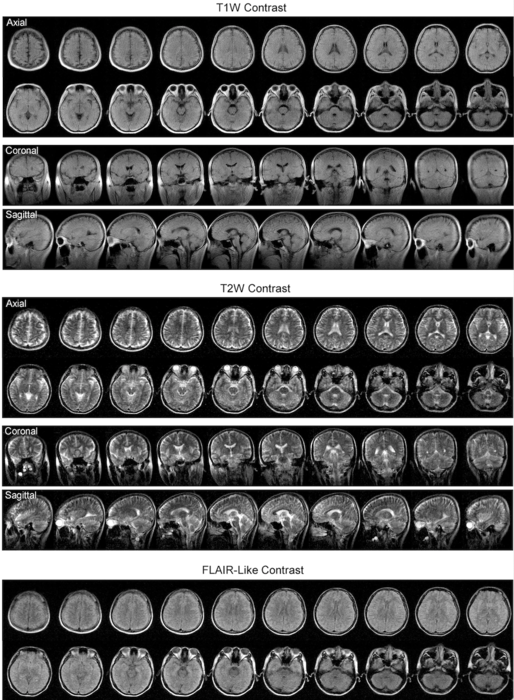

Researchers from the University of Hong Kong (HKU) have successfully developed a new magnetic resonance imaging (MRI) technology, the ultralow field (ULF) 0.055 Tesla brain MRI, which can operate from a standard AC wall power outlet and requires neither radiofrequency nor magnetic shielding room.

With the use of a deep learning algorithm, Professor Wu’s team has removed the constraint in conventional MRI, namely the need to be shielded from outside radiofrequency signal, which results in a bulky, non-mobile set-up. The existing MRI scanners are essentially a giant magnet, and need a purpose-built room to shield them from outside signals and to contain the powerful magnetic fields generated by their superconducting magnets, which require costly liquid helium cooling systems.

In collaboration with Professor Gilberto Leung of Neurosurgery and other clinicians at Queen Mary Hospital, his team had validated the results of using ULF-MRI by comparing them with images obtained from a standard 3 Tesla MRI machine. They could identify most of the same pathologies, including stroke and tumors results, despite the lack of clarity and resolution required for precision diagnostics.